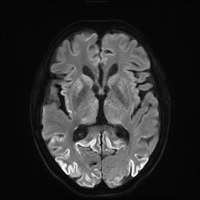

Creutzfeldt-Jakob-Krankheit, eine menschliche Prionenerkrankung // Creutzfeldt-Jakob-Disease, a human prion disease